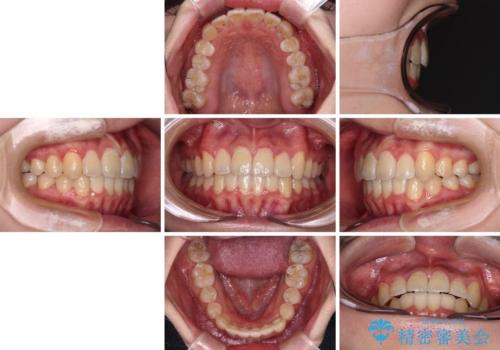

【モニター】八重歯と前歯のクロスバイト ワイヤーを併用しインビザラインで矯正治療

- 1年6ヶ月

インビザラインでの治療を希望されていましたが、前歯のクロスバイトや下顎小臼歯の捻転が認められたため、インビザライン単独で治療を行うよりも、ワイヤー装置を併用した方が、治療期間の短縮やトラブル回避できると判断し、ワイヤー装置を併用することとしました。

まずはワイヤー装置により前歯のクロスバイトと下顎小臼歯の捻転を改善し、その後インビザラインにより全体を整える矯正治療を行うこととしました。